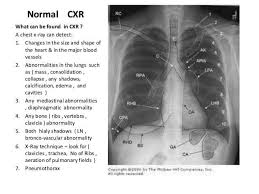

Interpretation of the chest x ray. Chest x ray is probably the most common imaging test. In addition to text and pictures, this tutorial contains interactive features which supplement the text and make it a more dynamic learning. Examination of the chest x ray is a process which requires a systematic approach. Standard frontal chest radiograph (roentgenogram) — upright; Recognizing normal anatomy on the cxr is key to understanding and interpreting abnormalities. Few providers (including mds) are comfortable interpreting their own films. In fact every radiologst should be an expert in chest film reading. Normal heart size is half of the chest width. Generally speaking, a normal cxr should have the lungs looking like zebras in that they are all black with strips. The aim of this study was to investigate the diagnostic accuracy of cxr interpretation by reporting radiographers (technologists). The chest radiograph remains the most important method of chest imaging, providing an easily accessible, inexpensive, quick, and effective diagnostic tool. Learn about chest x ray interpretation with free interactive flashcards.

Chest x ray is probably the most common imaging test. Standard frontal chest radiograph (roentgenogram) — upright; The aim of this study was to investigate the diagnostic accuracy of cxr interpretation by reporting radiographers (technologists). Normal heart size is half of the chest width. Generally speaking, a normal cxr should have the lungs looking like zebras in that they are all black with strips. A collection of data interpretation guides to help you learn how to interpret various laboratory and radiology investigations. It would be wrong to base a diagnosis on only the most obvious features of any chest x ray. In fact every radiologst should be an expert in chest film reading.

Normal heart size is half of the chest width. Few providers (including mds) are comfortable interpreting their own films. © 2005 adam guttentag, md. Chest x ray basic interpretation by vikram patil 37831 views. Generally speaking, a normal cxr should have the lungs looking like zebras in that they are all black with strips. The aim of this study was to investigate the diagnostic accuracy of cxr interpretation by reporting radiographers (technologists). Dr andrew dixon ◉ and dr jeremy jones ◉ et al. Recognizing normal anatomy on the cxr is key to understanding and interpreting abnormalities. It would be wrong to base a diagnosis on only the most obvious features of any chest x ray. Chest x ray is probably the most common imaging test. These images were saved with anonymous biodata for iom radiology collection and teaching purposes. Interpretation of the chest x ray. In addition to text and pictures, this tutorial contains interactive features which supplement the text and make it a more dynamic learning.